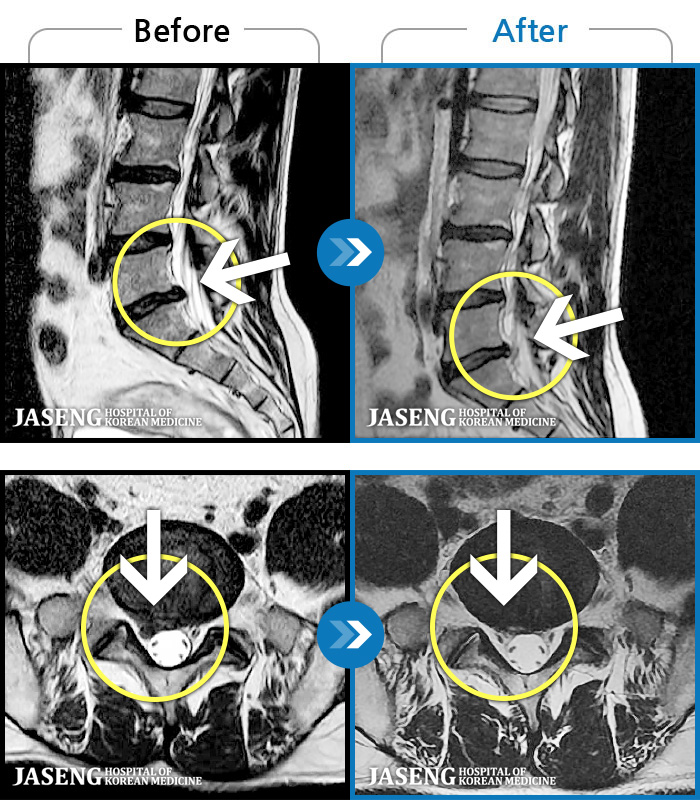

허리통증이 심해서 숙이기 어렵고 차에서 내리기 힘들었습니다.

2021.01.06 ~ 2025.03.10